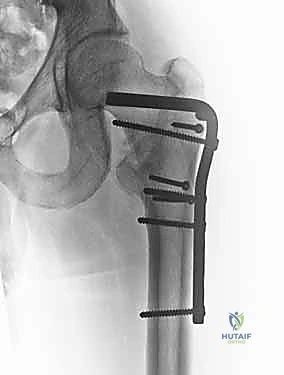

يعتمد اختيار نوع الجراحة على شكل الكسر، مدى تفتته، وجودة عظام المريض. يتقن الدكتور محمد هطيف أحدث تقنيات التثبيت الداخلي العالمية.

| آلية العمل | شريحة معدنية تُثبت على السطح الخارجي للعظم مع مسمار كبير يخترق عنق الفخذ. | مسمار من التيتانيوم يُدخل داخل التجويف النخاعي للعظم (من الأعلى) مع مسامير عرضية للتثبيت. |

| نوع الكسور المناسبة | الكسور المستقرة (Stable Fractures) ذات التفتت البسيط. | الكسور غير المستقرة (Unstable)، المفتتة بشدة، أو التي تمتد لأسفل العظم. |

| الشق الجراحي | شق جراحي جانبي أطول نسبياً (حوالي 10-15 سم). | جراحة طفيفة التوغل، شقوق صغيرة جداً (Minimally Invasive). |

| الميكانيكا الحيوية | يوفر ضغطاً ديناميكياً ممتازاً على موقع الكسر أثناء المشي. | يوفر دعماً ميكانيكياً أقوى لأنه يقع في مركز ثقل العظم (محور تحمل الوزن). |

| فقدان الدم | أكثر نسبياً مقارنة بالمسمار النخاعي. | أقل بكثير. |

| سرعة التعافي | ممتازة، ولكن قد تتطلب حذراً أكبر في الكسور غير المستقرة. | أسرع، ويسمح بتحميل الوزن في وقت أبكر في الحالات المعقدة. |

6. التثبيت النهائي (Locking)

لضمان عدم تحرك الغرسة، يتم تثبيتها بمسامير إضافية أصغر في جسم عظم الفخذ. هذه المنظومة الميكانيكية توفر ثباتاً استثنائياً يسمح للمريض بتحريك ساقه فور استيقاظه من التخدير.

مجموعة من الصور الإضافية التي توضح مراحل دقيقة من العمل الجراحي المعقد الذي يجريه الأستاذ الدكتور محمد هطيف لضمان أعلى درجات الدقة الميكانيكية الحيوية: